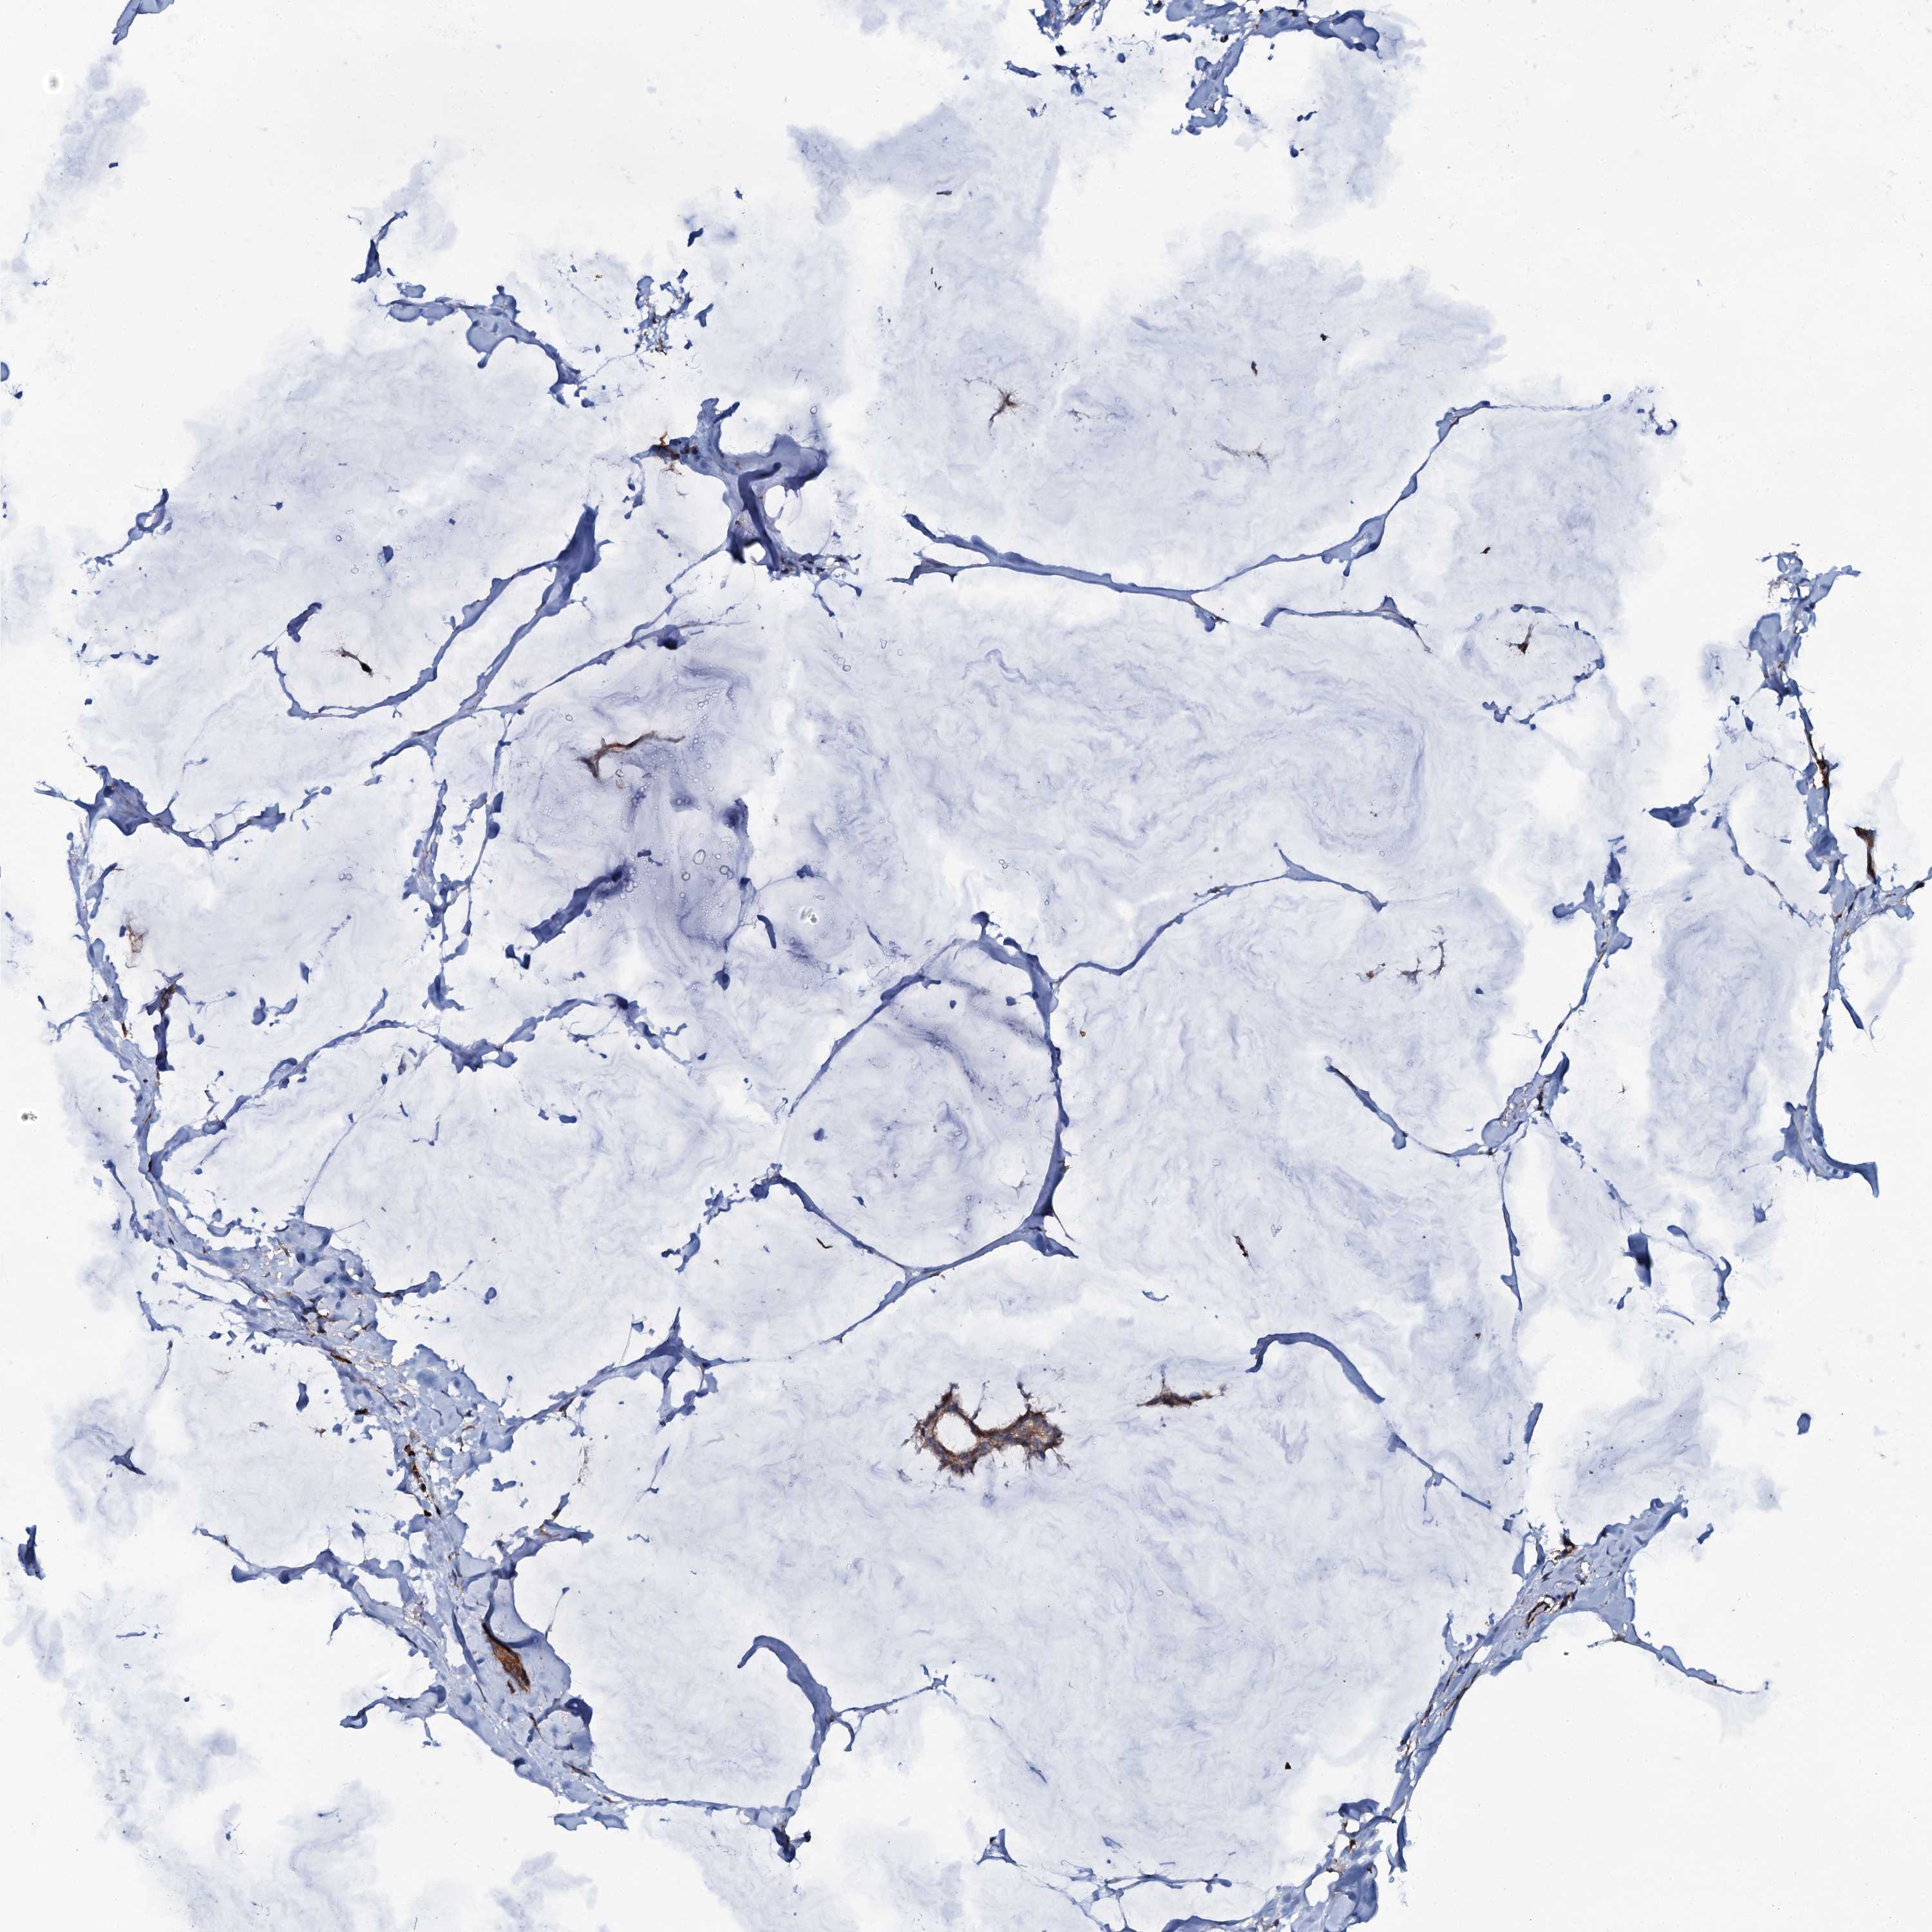

BRCA TCGA BRCA VALIDATION PROTEIN EXPRESSION